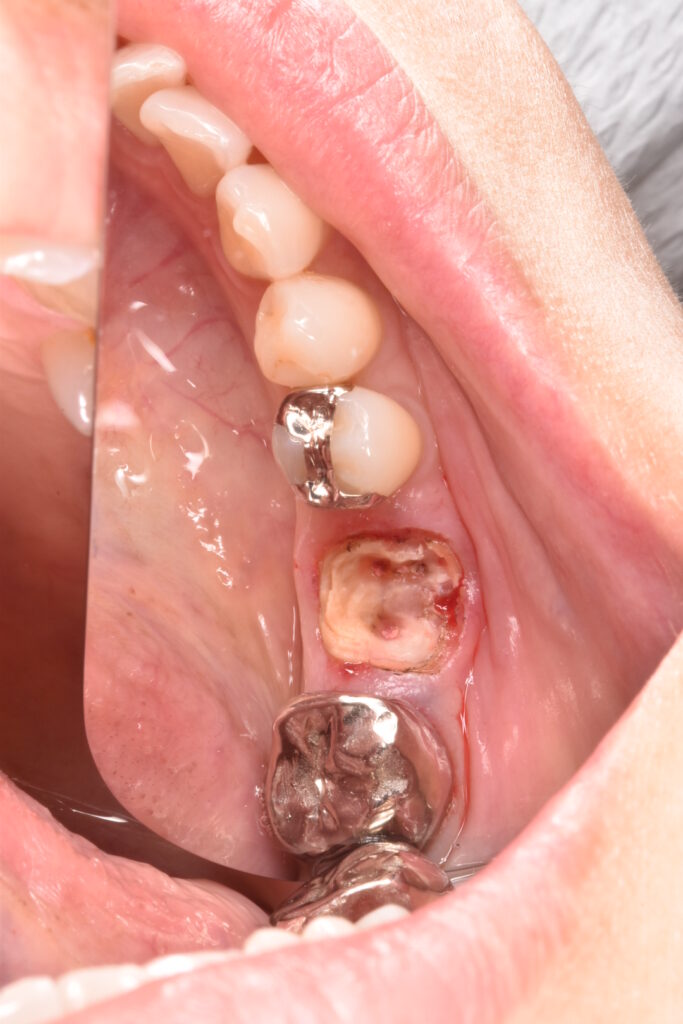

右下の前歯が差し歯でした。根本から折れていて一部が歯ぐきの中3ミリ近くに達しています。この破折縁から骨までは1ミリもなくこのままセラミックを被せても予後が悪いと説明させて頂きました。

こちらの写真は奥歯ですが、被せ物がとれ、抜歯に至ったケースです。特に奥歯では歯の根本深くから割れて取れることが多く、状況的にかなり悪いケースがあり、初診の方に「初めまして、この歯は抜歯です」と宣告せざるを得ないこともしばしばあります。